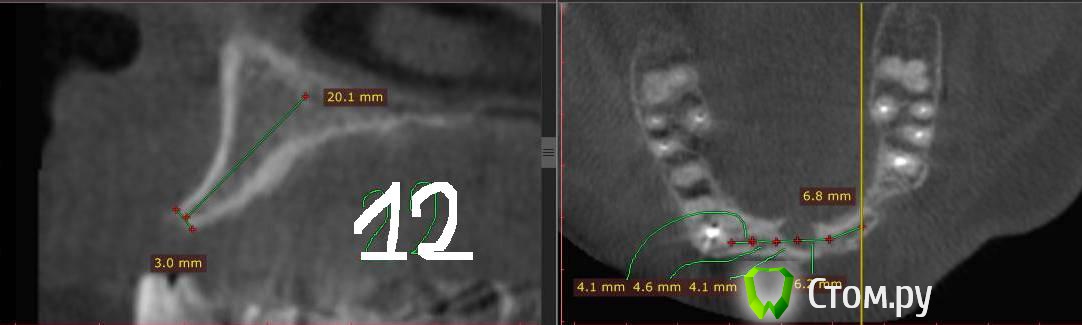

Togha Опубликовано 5 мая, 2014 Поделиться Опубликовано 5 мая, 2014 (изменено) Коллеги, обратился пациент, первый этап работы - устранение адентии между 14 и 23 зубами. По вертикали есть куда разбежаться (до анатомических образований от 17 и более мм), но вот гребень совсем узкий (от 2 до 5 мм), а также широкий резцовый канал (примерно 6.5 мм в диаметре). Между 14 и 23 расстояние 38 мм. Пациент решительно настроен на имплантацию. Хотел бы узнать, какую методику аугментации посоветуете, и как спозиционировать имплантаты? Склонялся к расщеплению гребня, нкр, имплантаты 3.75 мм на 10 мм, сделать мостик предлагает ортопед, на область 13, 11, 21, 22. Но как с расщеплением в зоне резцового канала и куда ставить имплантат 21 (как видно, есть значительное смещение канала от 11 в сторону 21), прямо в канал? Ссылка на DICOM файл http://yadi.sk/d/2vcbkBjaPBRgMСсылка на образ диска с просмотрщиком http://yadi.sk/d/csIsw0mYPBS2x На второй картинке примерно обозначен граница резцового отверстия вертикальными линиями Изменено 5 мая, 2014 пользователем Togha Ссылка на комментарий

Mane Опубликовано 6 мая, 2014 Поделиться Опубликовано 6 мая, 2014 Вы нарезали совсем ни то и ни так. Не разберешься на ваших срезах Ну никак. Нарежте и подпишите номер зуба. Нарежте зоны 13, 12, 22 Ссылка на комментарий